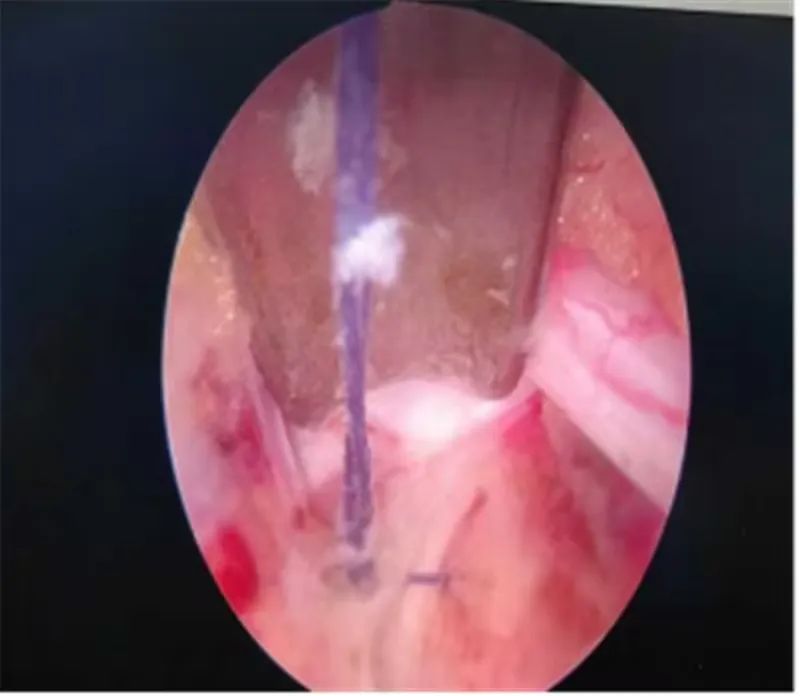

37岁的辛某某,腰臀部酸胀1年,左下肢放射性疼痛1月,曾在当地医院诊断为腰椎间盘突出症给予理疗、射频消融等治疗后症状缓解不明显,近1月来出现左下肢放射性疼痛,从臀部放射至大腿后侧、膝关节、小腿外侧,疼痛进一步加重,严重影响到患者的日常生活。不能下地活动,为寻求进一步治疗,来到市星元医院就诊。经过专科查体及影像学辅助检查,患者被诊断为腰椎间盘突出症、腰椎管狭窄症。邢永军主任医师团队综合评估患者病情,结合患者年龄、椎管狭窄程度、椎间盘退变程度、椎间隙高度等各项指标,经与患者充分沟通,开放手术创伤太大,单轴内镜受灵活性所限,不一定能够达到手术目的,“AUSS是传统脊柱手术内镜化方案,兼具开放手术和内镜手术的优势,且创伤比双通道的UBE手术更小,是目前最好的选择!,制定了“AUSS关节镜辅助单孔脊柱手术”的治疗方案。术中,医生通过可视化内镜辅助对患者狭窄的椎管进行减压、突出椎间盘进行摘除,对破裂的纤维环进行缝合,提高患者术后生活质量,术后患者恢复良好。下肢放射性疼痛完全消失。

AUSS技术即关节镜辅助单切口脊柱手术,是目前新兴的脊柱内镜技术,结合了UBE技术与孔镜技术的优点,是单轴内镜技术的延续、UBE双通道技术的改进、开放手术内镜化的体现,是将工作通道与观察通道置于同一软性切口内,具有减压范围广、操作空间大、定位简单、透视少等特点,30度关节镜,视野范围广,镜头360度自由转动,减少操作盲区;不同内镜技术的结合:关节镜的三角操作以及后路同轴内镜的同轴摆动、旋转,以及非同轴旋转技术。